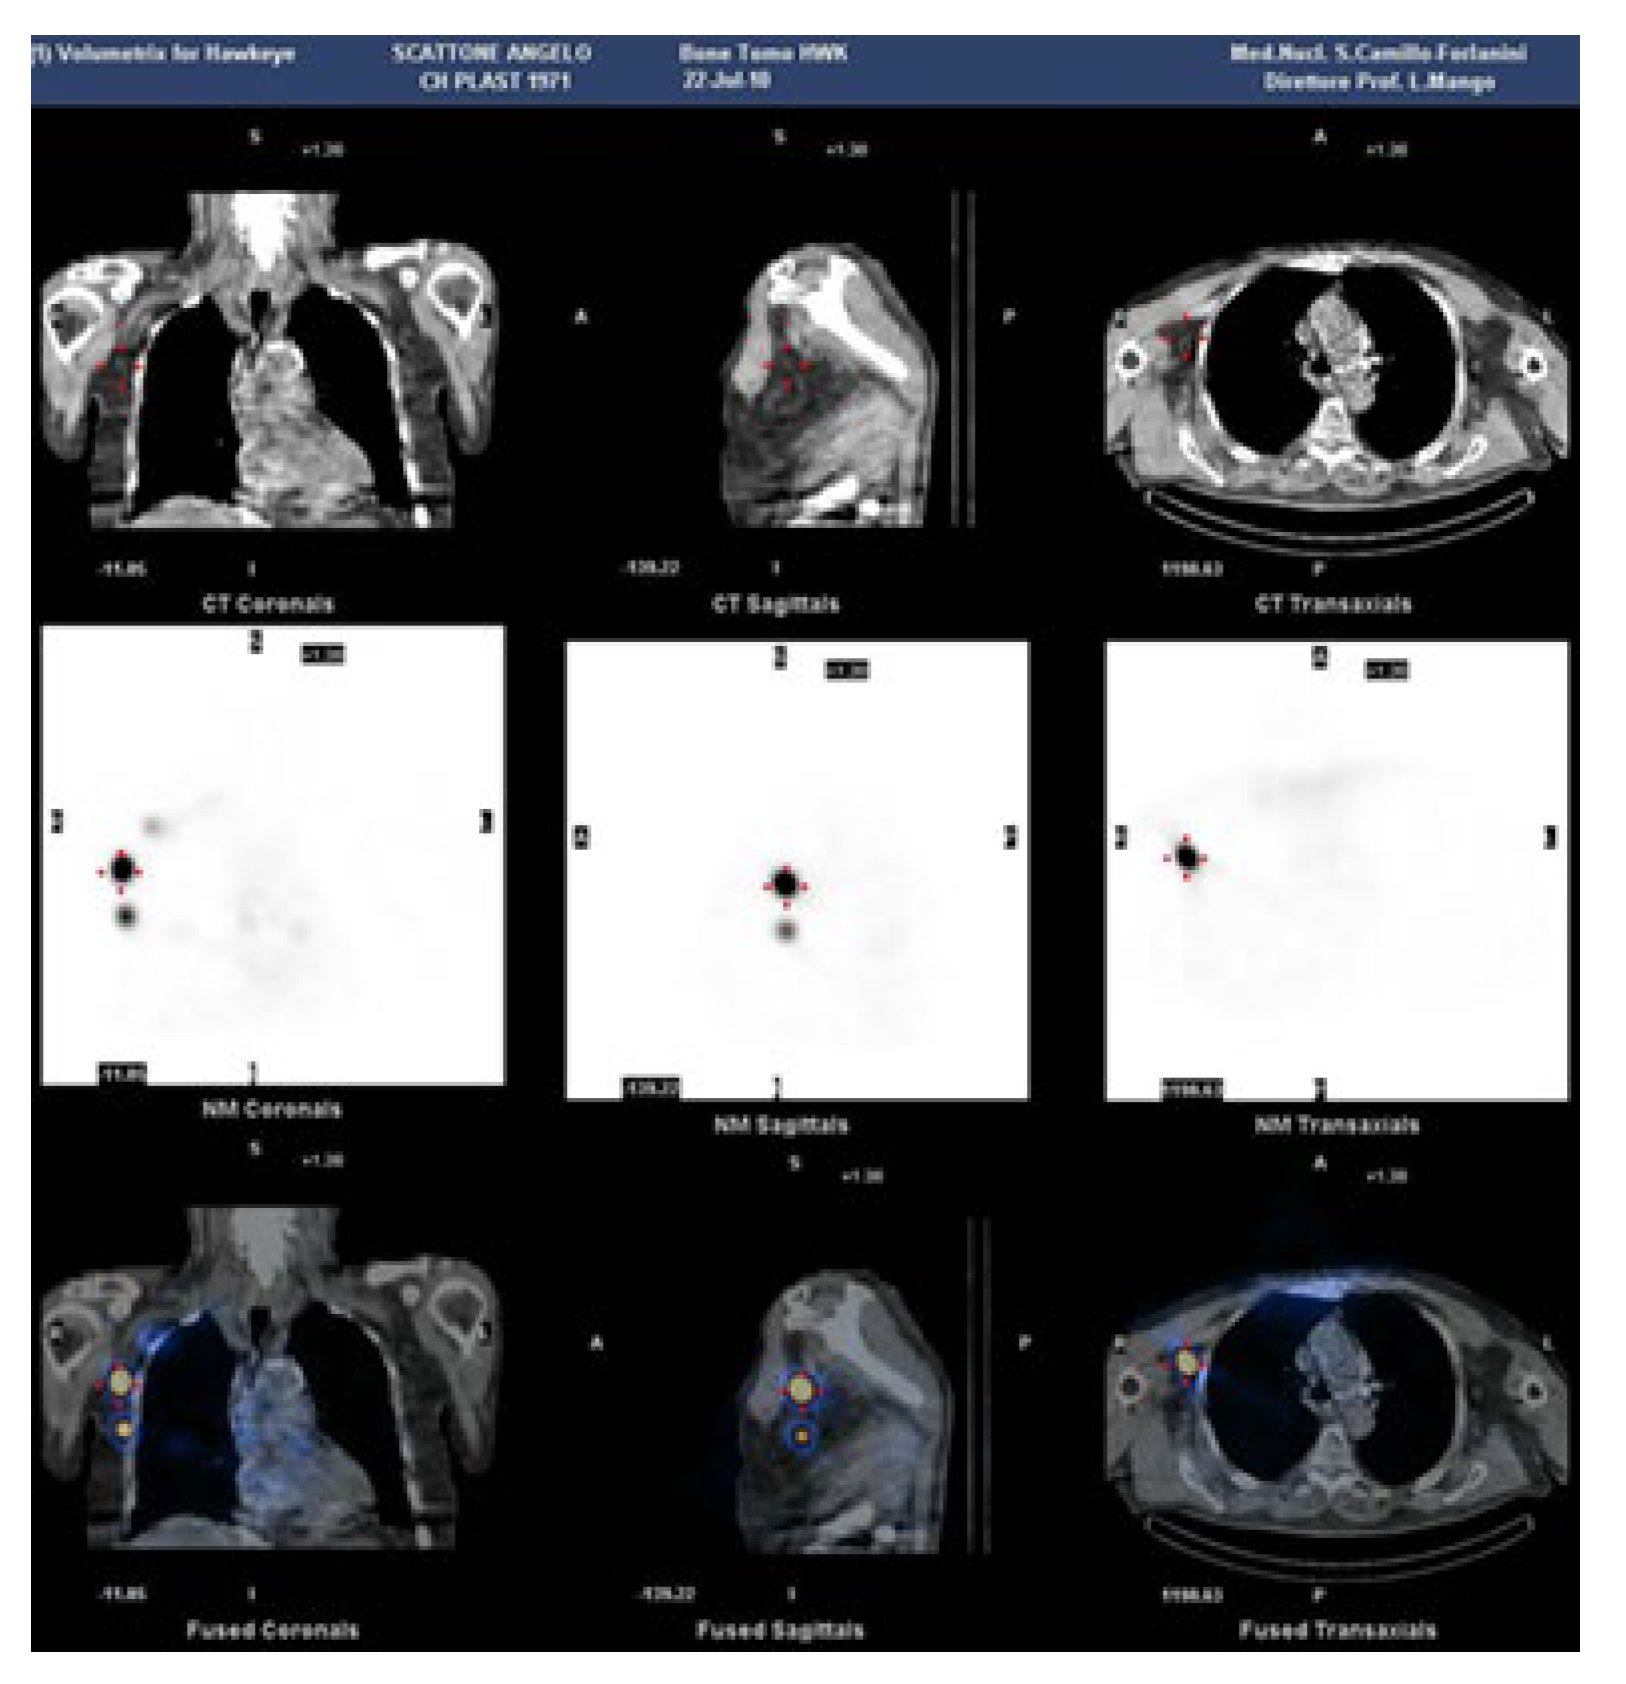

The use of tomographic projections (SPECT) in addition to planar ones for lymphoscintigraphy certainly provides greater information on deep alterations. But the real breakthrough came with the use of hybrid machines capable of simultaneously combining CT and SPECT imaging, to offer functional information (with SPECT) along with anatomical images (CT) [26].

Lymphoscintigraphy SPECT-CT of the axillary region, has been employed to evaluate the impact of including, as target volumes in the radiation treatment plan, the lymph nodes involved in arm drainage that might affect lymphedema [27] (Figure 2).

Figure 2. SPECT/CT lymphoscintigraphy of the chest.